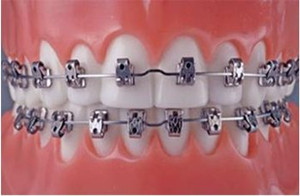

4.金属托槽矫治技术

详细介绍:金属托槽矫正的优点是技术非常成熟,矫正过程中移动牙齿的效率非常高,医生可以非常准确的控制牙齿位置,较终能达到很好的矫正效果,而且其价格比较低。